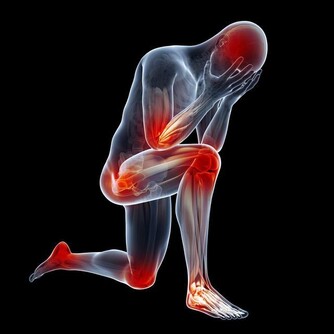

俗話說得好:「病來如山倒;病去如抽絲」...實際上,任何疾病的發生發展都有一個過程,在突發前都有一些身體上的先兆,只不過沒有引起我們足夠的重視罷了。隨著健康意識的增強,我們應該對人體發出的不良信號,給予足夠的重視,避免釀成大禍. 翻拍wikihow 一、起床後的四個信號 人的一天在不同階段身體的不良感受,就是在向您的健康發出警示信號。 1、清晨醒來如果頭暈、頭昏,可能是出現了頸椎骨質增生或血黏度過高等疾病; 2、如果在起床活動20分鐘後浮腫還不徹底消失,提示可能有腎病或心臟病; 3、晨起噁心嘔吐,除去懷孕的原因,如每天早上都如此,很可能是慢性胃炎或肝膽有病; 4、晨起小便,如果尿液棕色,提示肝臟可能出現問題。 二、清晨對鏡觀察臉色 洗臉時對著鏡子觀察,看看自己的臉色有沒有什麼異常: 1、如果發現自己臉色潮紅,可能與心臟病或高血壓有關; 2、如臉色帶黃,還伴以身體疲倦,很可能是黃疸型肝炎; 3、如發現眼睛顏色改變,充血、渾濁、色黃,應馬上去醫院看醫生; 4、如眼瞼蒼白,提示可能患了缺鐵性貧血; 5、如眼角膜出現一圈模糊的灰環,說明心臟可能有問題,如果是30—50歲的男性應馬上到醫院就診。 三、刷牙留意牙齒口氣 1、刷牙時如果牙齦出血,很可能是牙周病,因為如果牙齒健康是不會出血的。牙齒出血也可能與肝病有關。這種現象在慢性肝病患者中很普遍,還會伴有鼻子流血、月經過多。主要原因是肝細胞損傷後,肝臟產生凝血因子的功能下降,繼而凝血機制發生障礙。一般牙出血的肝炎病人可以服用維生素C、維生素K及其他止血藥來緩解病情。 2、如果出現口臭、口氣重,則可能是牙周病引起,同時,胃病、肝病、糖尿病等全身性疾病或缺乏微量元素鋅和維生素B都可能導致口臭。比如,胃幽門螺桿菌感染可引起持續性口臭,還常伴有不同程度的飢餓感和胃痛。一旦吃飽喝足,口臭會隨之減輕,而隨著幽門螺桿菌的根治,口臭也會自動消失。 3、口中有氨味要格外注意腎臟的健康。當腎功能衰竭時,由於不能正常代謝,體內肌酐、尿素氮含量增高,口中就有一股特殊的氨氣味。 四、飲食上的大病先兆 1、如果總感到口渴,要去查查血糖和糖耐量,看有沒有可能是糖尿病; 2、如果在清晨4—5點鐘醒來有強烈的心慌飢餓感,並且伴有疲乏無力,直到吃早餐後不舒適的感覺才逐漸消失,提示可能是糖尿病傾向; 3、如果吃油膩食物後上腹部疼痛,並放射到右肩背部,很可能是患有肝膽疾病; 4、如果食慾亢進,體重卻減輕,可能患了甲狀腺功能亢進症; 5、如果沒有食慾,見到油膩就噁心,易疲勞,可能是患了肝炎; 6、如果出現食不知味,並伴心悸、多夢、失眠等。這就意味著心臟功能受到了損害,是操勞過度所致。當口中乾澀,舌苔厚重,嘗不出食物的滋味時,尤其要警惕,防止心臟發生病變; 7、如果飯後總是出現反酸、腹脹或腹痛等症,提示積食了,要多吃新鮮蔬菜,三餐要注意清淡,以易於消化。 五、手部的警示信號 1、觀察自己的雙手,如果發現指尖比指節更粗大,可能是患有較嚴重的肺部疾病; 2、如果指甲生長緩慢,沒有光澤並且變黃變厚,提示淋巴系統出了毛病; 3、如果手背靜脈突出,並且隨著年齡增加越加明顯,也提示有心臟病的可能; 4、如果手掌泛紅,可能是肝臟出現問題及內分泌失調; 5、如果過度興奮或緊張時手掌常潮濕出汗,可能有甲狀腺的異常; 6、手發抖可能是甲亢,也可能是帕金森病。 六、眼睛的警示信號 1、眼睛發花,眼角乾澀,看不清東西。這是肝功能衰弱的先兆。如果按一按肝臟四周,就會有發脹的感覺,這時除了及時就醫外,還要注意用眼衛生,不要讓眼睛太疲勞; 2、如果經常眼睛疼痛,除了用眼疲勞外,老年人出現這種情況要提防青光眼。